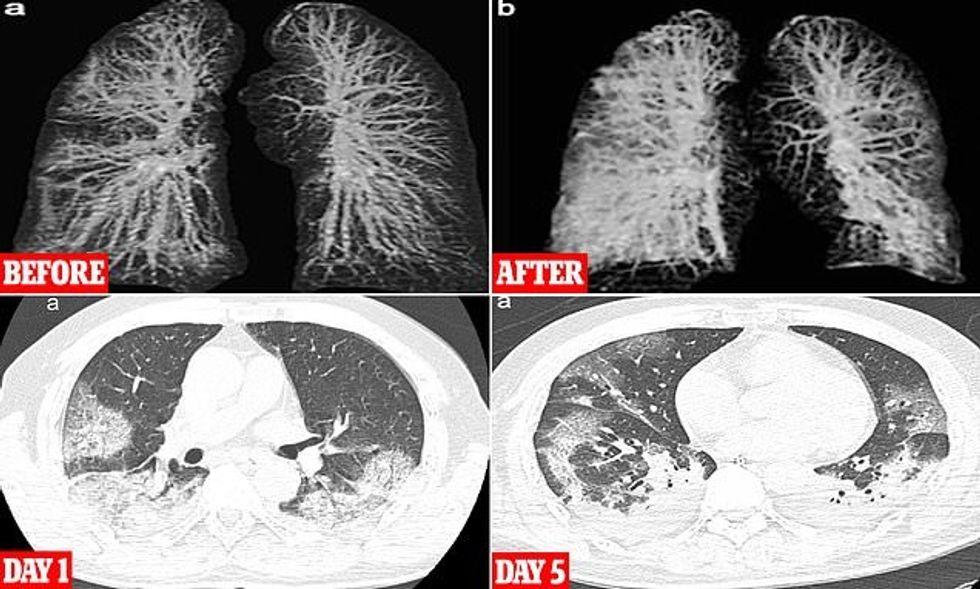

"Shtresa mbrojtëse e këtyre organeve të frymëmarrjes është e dëmtuar, gjë që çon në inflamacion. Kjo shkakton acarim nervor dhe madje një sasi e vogël pluhuri mund të shkaktojë kollitje. Nëse kollitja përkeqësohet, acarimi përhapet në njësitë e shkëmbimit të gazit të vendosura në fund të rrugëve të frymëmarrjes. Nëse infektohen, ata përgjigjen duke nxjerrë materiale nga pezmatimi në qeset e ajrit që ndodhen në fund të mushkërive”, shpjegon Wilson.

Mushkëritë me materiale si rezultat i inflamacionit nuk arrijnë të japin oksigjen të mjaftueshëm në gjak, gjë që zvogëlon aftësinë e trupit për të marrë oksigjen dhe lëshuar dyoksid karboni.